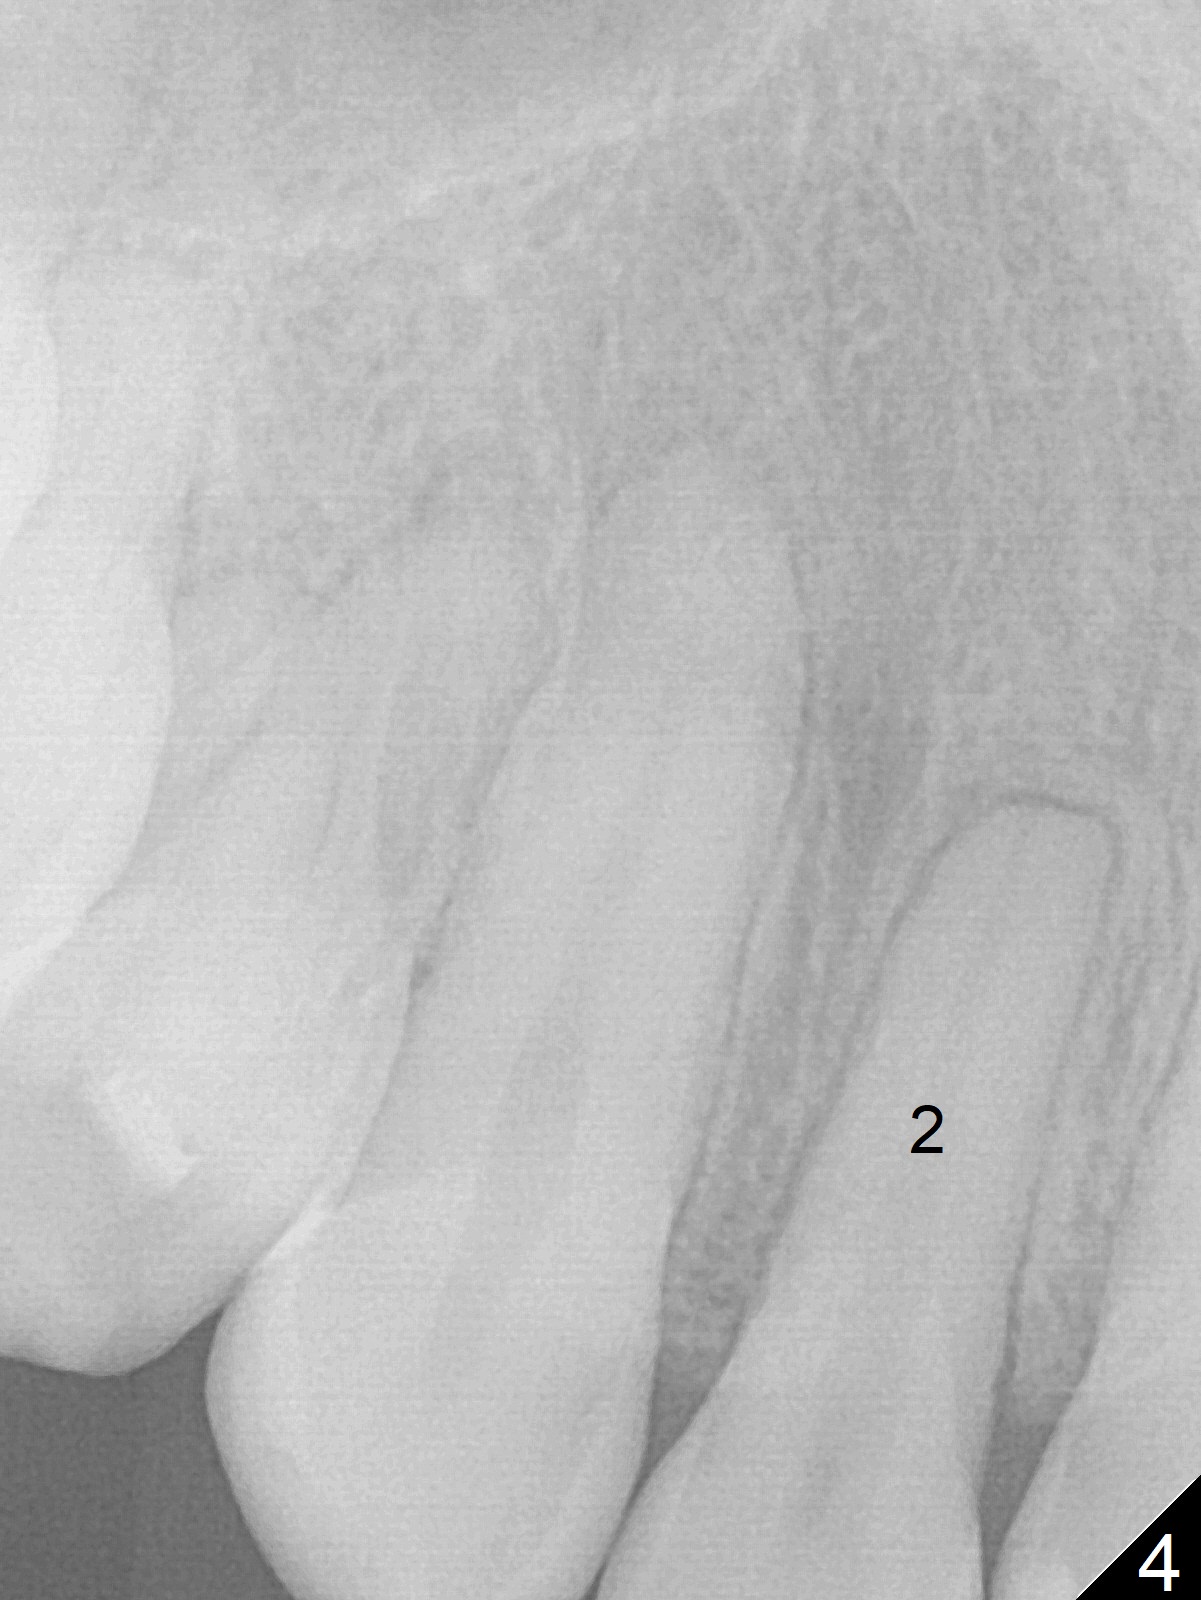

Discoloration of Upper Canines and

1st Bicuspids

Five months post debanding, the upper right canine becomes transiently symptomatic (tender to touch). Although both the right (Fig.1) and left (Fig.2) canines (3) and 1st bicuspids (4) discolor, the right ones are necrotic (pulpal test). It appears that these two teeth have periapical radiolucency (Fig.3,4), while the lateral incisor has shortened root (2). The longest tooth (upper canine) appears to be the most vulnerable to trauma associated with orthodontic movement.